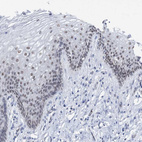

Immunohistochemical staining of human testis shows strong nuclear positivity in Leydig cells.